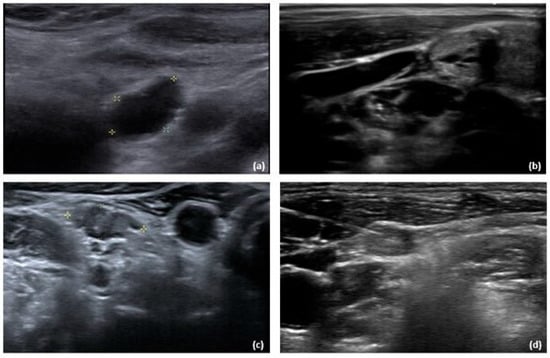

| Follow-up LNs | ||||

| Size, mm | 8 (4) | 7.5 (3.7) | 8 (4) | 0.873 |

| Calcification (yes/no) | [3/60] | [3/19] | [0/41] | 0.039 |

| Cystic content (yes/no) | [7/56] | [4/18] | [3/38] | 0.281 |

| Hyperechoic content (yes/no) | [14/49] | [6/16] | [8/33] | 0.534 |

| Absence of hilum (yes/no) | [38/25] | [17/5] | [21/20] | 0.060 |

- Jiang, H.J.; Wu, C.W.; Chiang, F.Y.; Chiou, H.Y.; Chen, I.J.; Hsiao, P.J. Reliable sonographic features for nodal thyroglobulin to diagnose recurrent lymph node metastasis from papillary thyroid carcinoma. Clin. Otolaryngol. 2018, 43, 1065–1072. [Google Scholar] [CrossRef] [PubMed]

- Lee, S.; Lee, J.Y.; Yoon, R.G.; Kim, J.-h.; Hong, H.S. The value of microvascular imaging for triaging indeterminate cervical lymph nodes in patients with papillary thyroid carcinoma. Cancers 2020, 12, 2839. [Google Scholar] [CrossRef]